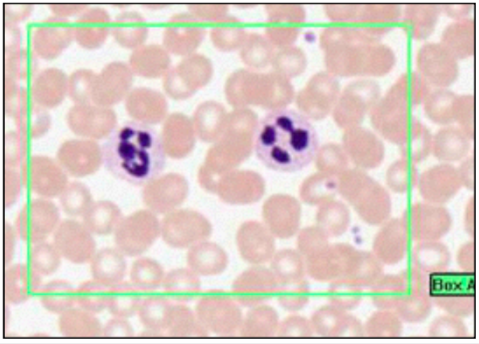

EOSINOPHILS (ROMANOVSKY/LEISHMAN’S)

- 2-3 lobe nucleus

- bright pink granules

- acidophils

- circulate for a few hours

- diurnal - highest in morning

- phagocytose antigen/antibody complexes, associated w/ parasitic infection

- neutralise histamine